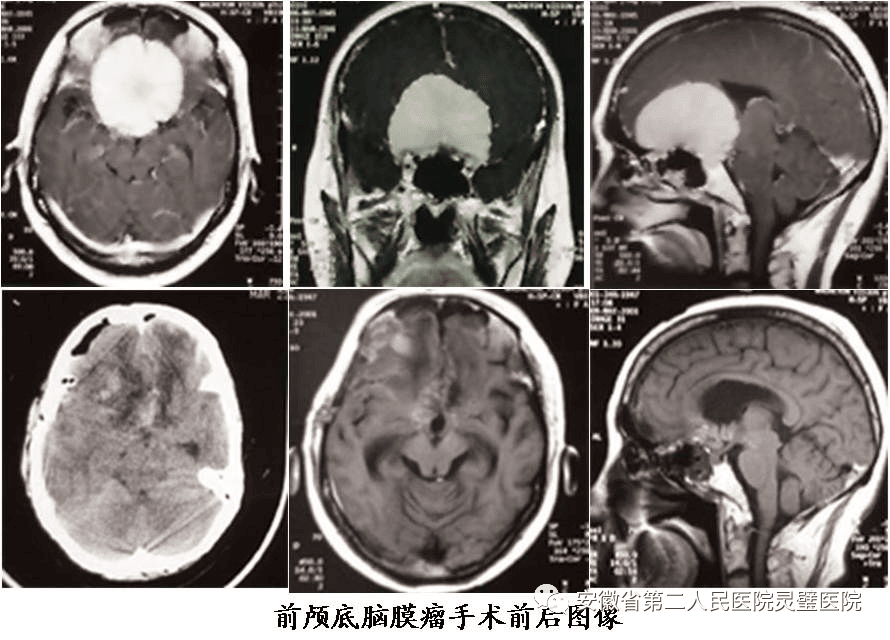

二、神经肿瘤的综合治疗技术

常规开展各型颅内及脊髓肿瘤手术,包括鞍区肿瘤、斜坡肿瘤、后颅窝等颅底肿瘤,尤其在听神经瘤、颅咽管瘤、垂体瘤等治疗方面处于国内领先水平。系统开展胶质瘤的综合治疗,并结合肿瘤基因指标,提升胶质瘤的放化疗效果,极大提高5年的存活率。

垂体瘤手术前后

岩斜区脑膜瘤术前及术后